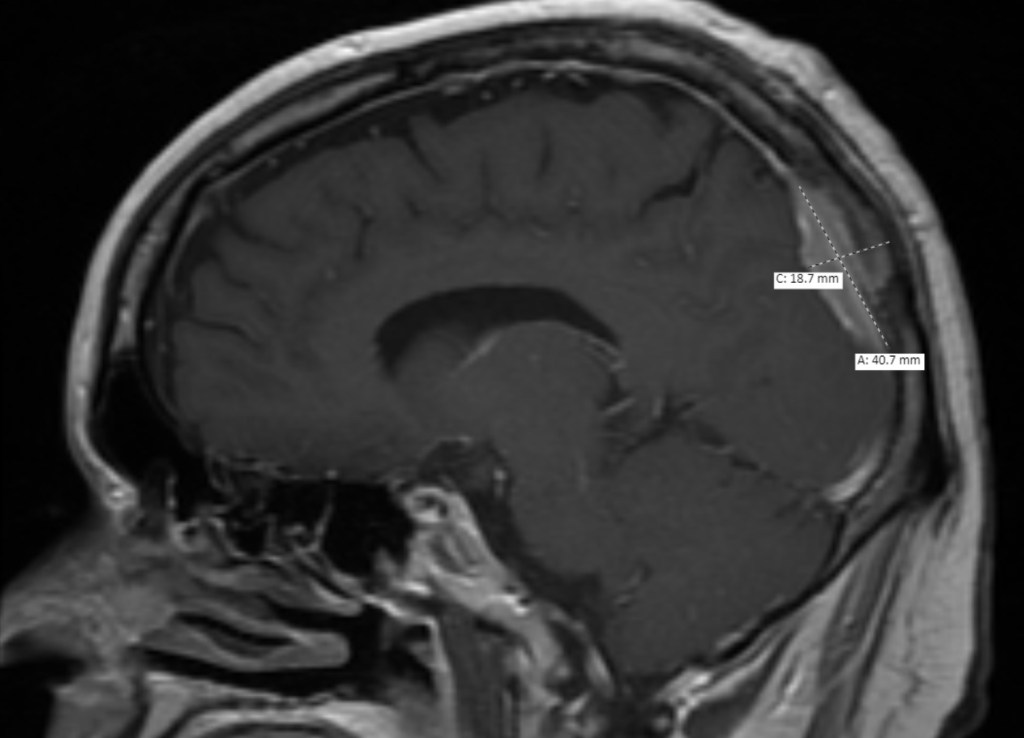

The MRI looked good. Since they couldn’t take out the whole tumor without cutting into that main blood vessel they showed how small his Neurosurgeon was able to get it which looks like it was 2.1cm X 0.9 cm. Beyond that, everything looks on track for a person who had surgery 24 hours ago.

To remind everyone about the size and location of the tumor